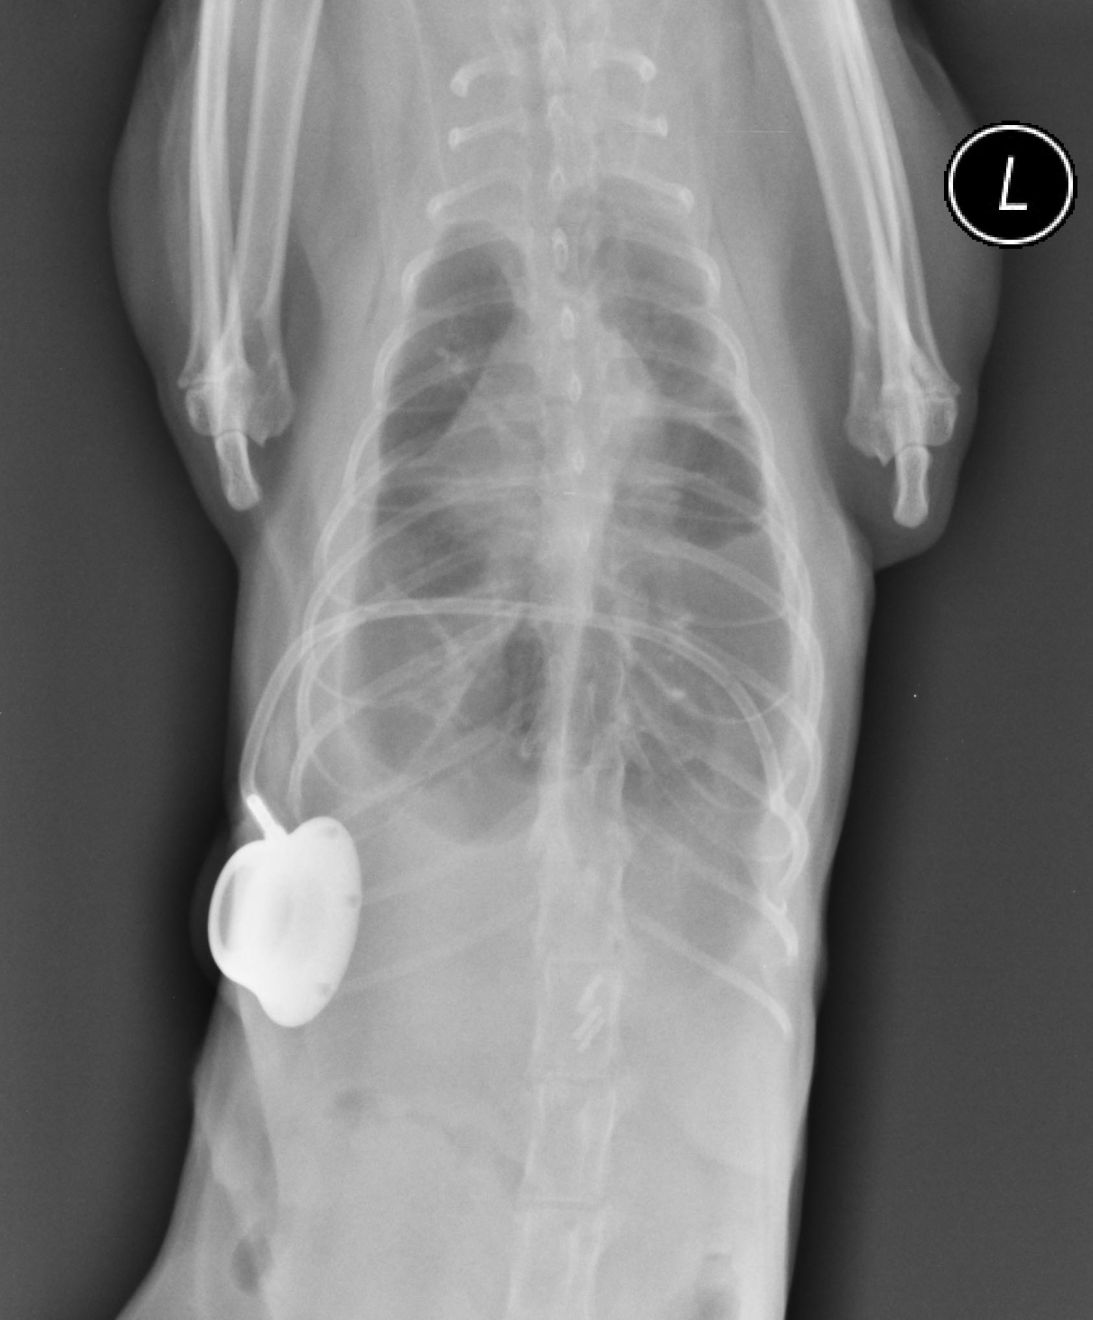

A pleuro-port

A pleuro-port, as seen on these post-surgery radiographs

Abbildung 5. Diese beiden postoperativen Röntgenaufnahmen zeigen einen Pleuro-Port, der dazu dient, eine Thorakozentese zu Hause zu ermöglichen oder das Risiko einer Traumatisierung durch wiederholtes Einstechen von Kanülen für die häufige Drainage eines rezidivierenden Ergusses zu reduzieren. © Elizabeth Rozanski